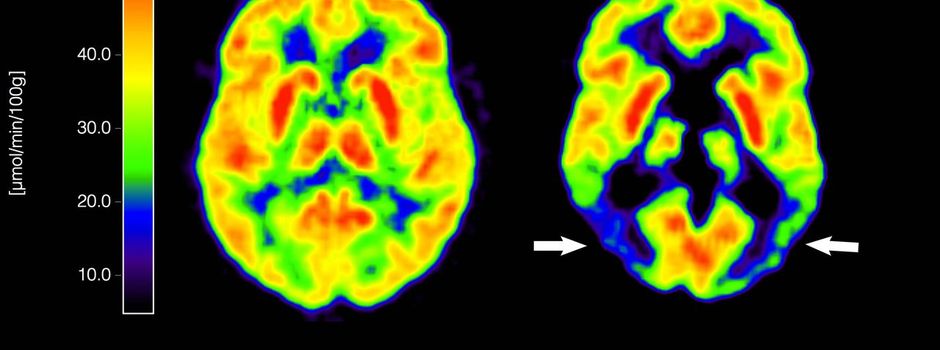

Bisherige Alzheimer-Therapien behandeln nur Symptome der Krankheit, nicht ursächliche Prozesse im Gehirn. Das ist bei Lecanemab anders: Der Antikörper richtet sich gegen Amyloid-Ablagerungen im Gehirn und soll dadurch den Verlauf der Krankheit verlangsamen. Um Heilung oder Verbesserung geht es allerdings auch bei diesem Wirkstoff nicht, ein solches Mittel ist weiterhin nicht in Sicht.

Die erfassten Schwellungen und Mikroblutungen im Gehirn blieben überwiegend ohne Symptome und wurden zumeist erst durch bildgebende Verfahren wie Magnetresonanztomographie (MRT) bemerkt. Insbesondere bei wiederholtem Auftreten drohen jedoch eine verminderte Gehirnleistung oder Koordinationsschwierigkeiten. Mikroblutungen gelten zudem als Risikofaktor für größere, potenziell lebensbedrohliche Hirnblutungen.

Die EMA betont darum in ihrer Stellungnahme, dass es zwingend Maßnahmen zur Risikominimierung geben müsse. Vor Beginn der Behandlung und vor der 5., 7. und 14. Lecanemab-Dosis müssen bei den Patienten demnach MRT-Scans durchgeführt werden, zusätzliche Scans bei Warnzeichen wie Kopfschmerzen, Sehstörungen und Schwindel. Auch die Behandlung selbst ist aufwendig: Lecanemab wird als intravenöse Infusion alle zwei Wochen verabreicht.